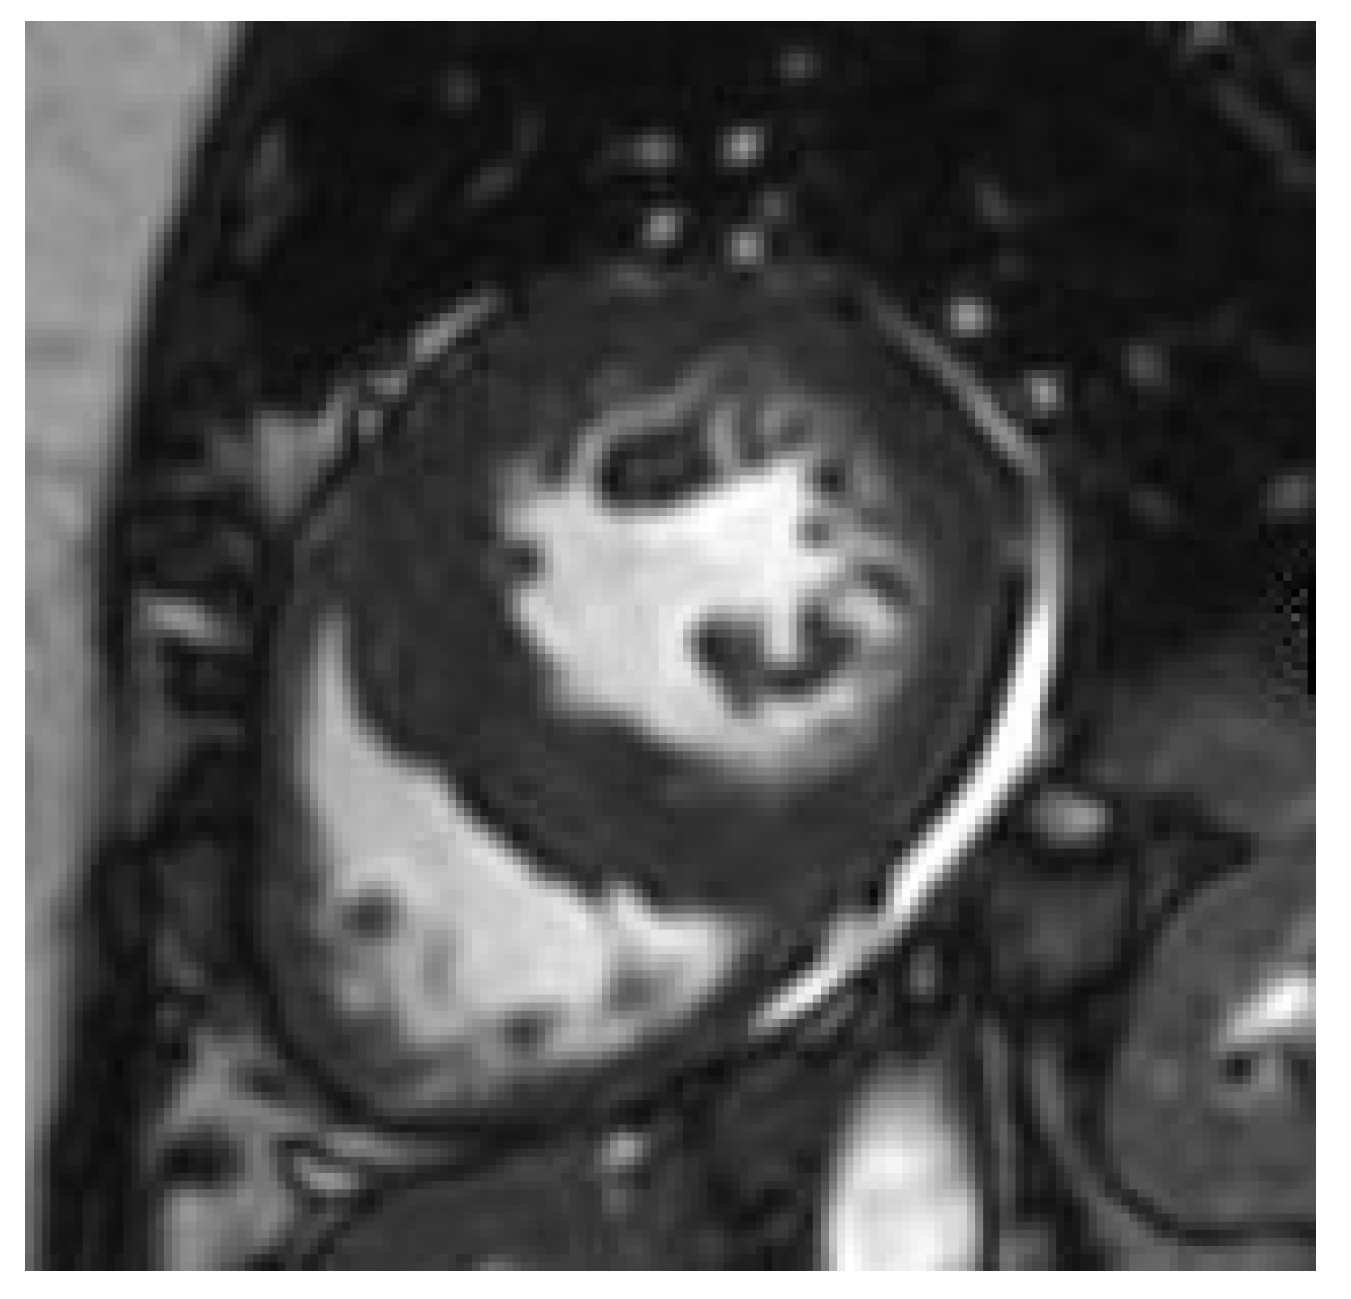

2.4. The Emerging Role of CMR in Obesity

- Heydari, B.; Jerosch-Herold, M.; Kwong, R.Y. Assessment of Myocardial Ischemia with Cardiovascular Magnetic Resonance. Prog. Cardiovasc. Dis. 2011, 54, 191–203. [Google Scholar] [CrossRef]

- Shah, R.V.; Heydari, B.; Coelho-Filho, O.; Abbasi, S.A.; Feng, J.H.; Neilan, T.G.; Francis, S.; Blankstein, R.; Steigner, M.; Jerosch-Herold, M.; et al. Vasodilator Stress Perfusion CMR Imaging Is Feasible and Prognostic in Obese Patients. JACC Cardiovasc. Imaging 2014, 7, 462–472. [Google Scholar] [CrossRef] [PubMed]

- Jing, L.; Binkley, C.M.; Suever, J.D.; Umasankar, N.; Haggerty, C.M.; Rich, J.; Nevius, C.D.; Wehner, G.J.; Hamlet, S.M.; Powell, D.K.; et al. Cardiac remodeling and dysfunction in childhood obesity: A cardiovascular magnetic resonance study. J. Cardiovasc. Magn. Reson. 2016, 18, 28. [Google Scholar] [CrossRef]

- Jing, L.; Pulenthiran, A.; Nevius, C.D.; Mejia-Spiegeler, A.; Suever, J.D.; Wehner, G.J.; Kirchner, H.L.; Haggerty, C.M.; Fornwalt, B.K. Im-paired right ventricular contractile function in childhood obesity and its association with right and left ventricular changes: A cine DENSE cardiac magnetic resonance study. J. Cardiovasc. Magn. Reson. 2017, 19, 49. [Google Scholar] [CrossRef] [PubMed]